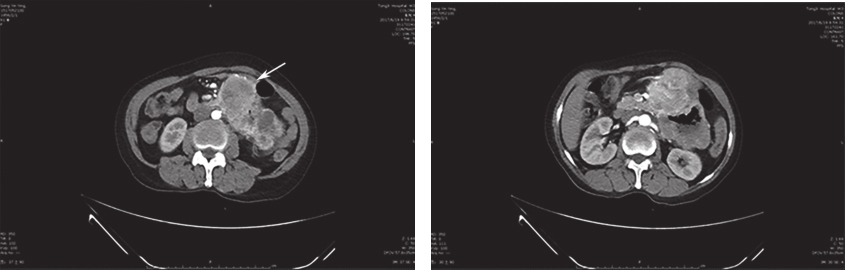

腹部增强CT:近段空肠肠壁明显增厚,可见团块样混杂密度影,最大截面约为10.6cm×7.3cm,动脉期可见明显不均匀强化,由肠系膜上动脉分支供血,多考虑为肿瘤性病变,胃肠间质瘤可能;肝左外叶低密度灶,建议定期复查;盆腔少量积液(图1)。

图1 腹部增强CT

上腹巨大包块与十二指肠分界欠清